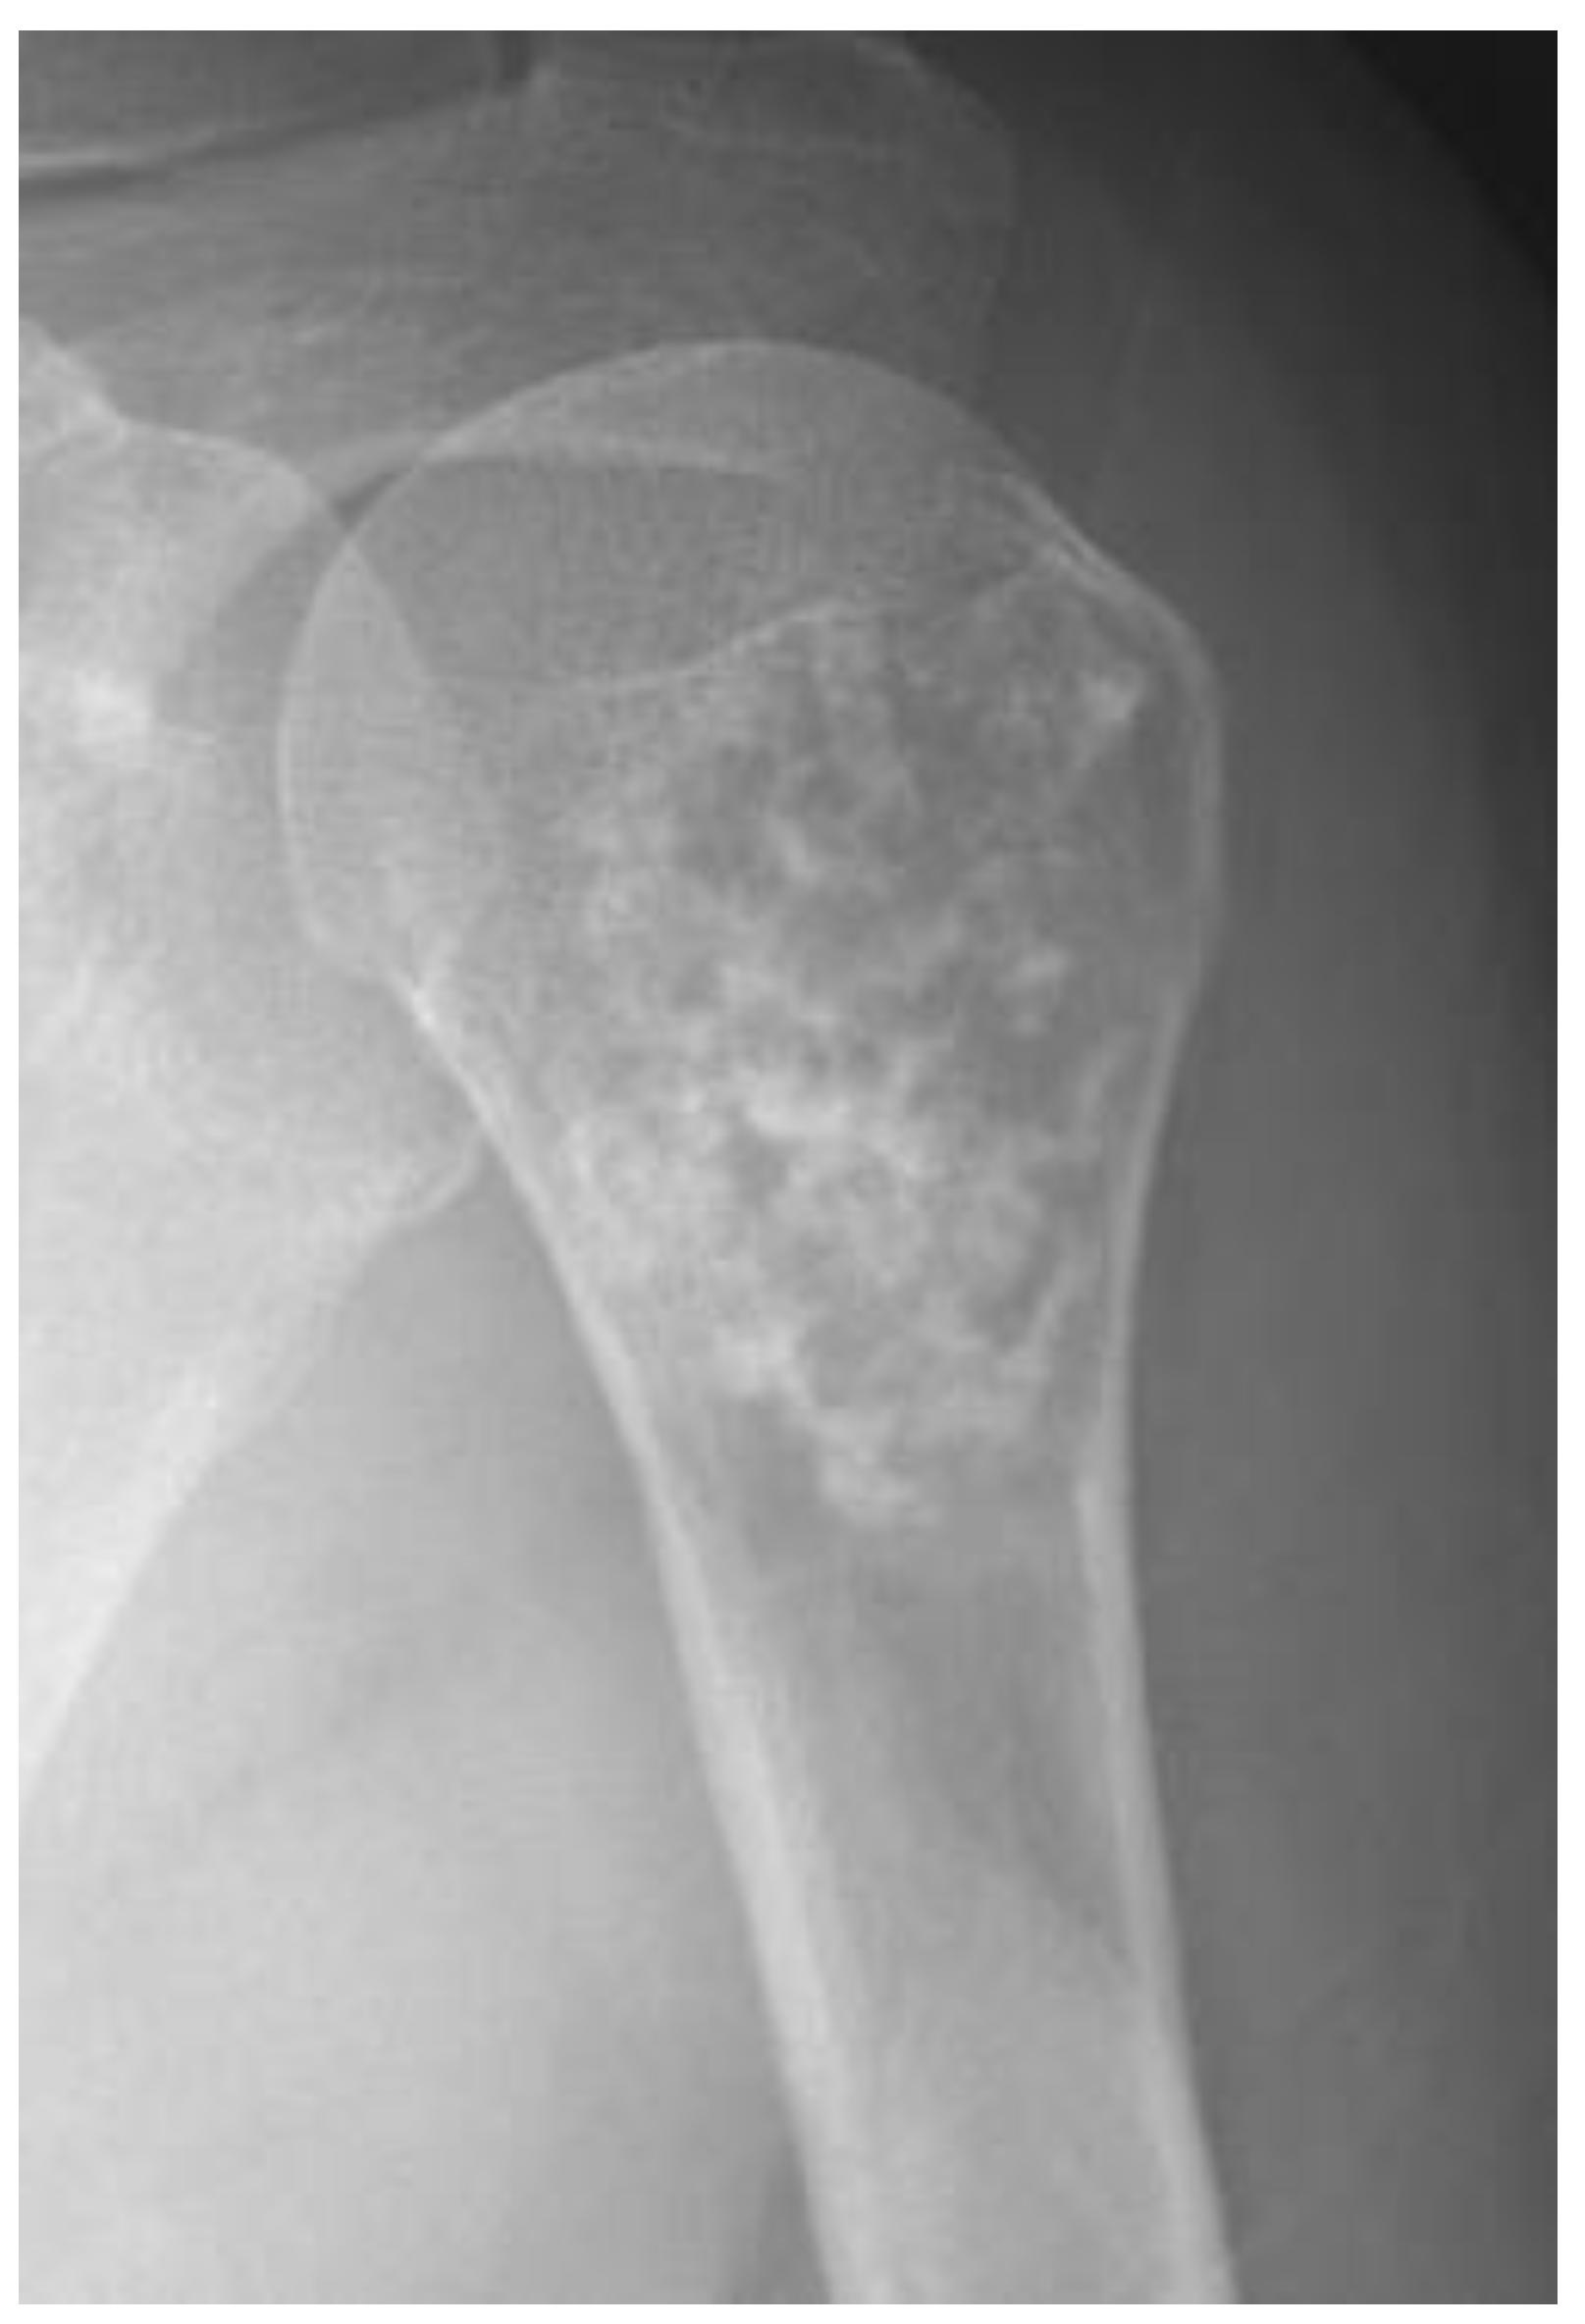

Radiographs of conventional chondrosarcomas typically reveal a mixed lytic and sclerotic appearance [1,5]. The sclerotic areas represent chondroid matrix mineralization, which is seen in 60–78% of lesions [1]. Well-differentiated tumors tend to have a characteristic ring-and-arc pattern (Figure 2), whereas higher-grade chondrosarcomas often contain relatively less matrix mineralization and have a more amorphous or stippled appearance [1,5,19,21,22,23]. It is vital to differentiate benign from malignant cartilage tumors; increased biological activity presents as deep and extensive endosteal scalloping as an attempt of tumor cell extension to a second compartment [1].

Figure 2.

Atypical cartilaginous tumor of the humerus in a 59-year-old woman. Anteroposterior shoulder radiograph shows a mixed lytic and sclerotic lesion in the humerus. The sclerotic component represents typical chondroid ring-and-arc calcification.